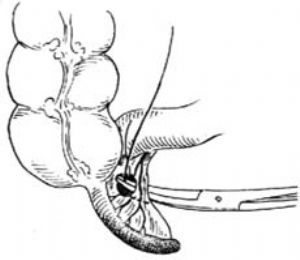

3.當闌尾位於盲腸後,位置固定不易切除時,可切開盲腸外下方的後腹膜[圖3 ⑴],再用紗布包住盲腸向上翻轉,露出闌尾後,作逆行闌尾切除術。另若闌尾較長伴管端粘連固定,不宜按常規勉強提出末端,改爲逆行切除闌尾。先用變止血鉗在靠近闌尾根部處穿過其系膜,帶過兩根4-0號絲線,雙重結紮闌尾根部[圖3 ⑵]。在結紮遠端1cm處夾一把彎止血鉗,用刀在止血鉗與結紮線之間切斷。闌尾殘端消毒處理後,根據具體情況行荷包縫合包埋或褥式縫合包埋。再用彎止血鉗向闌尾尖端方向分段鉗夾、切斷闌尾系膜[圖3 ⑶]最後切除闌尾,一一結紮近端闌尾系膜。

⑵結紮闌尾根部